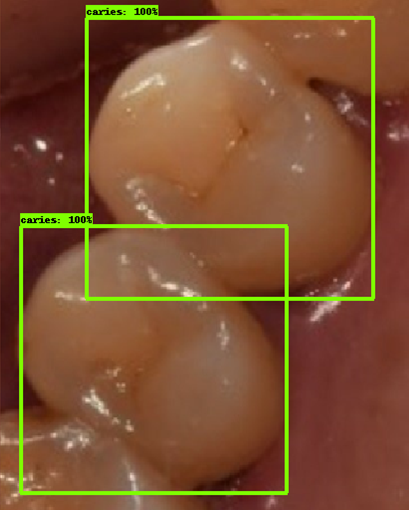

- 인식이 잘 되지 않은 케이스들을 보면, 사람의 눈으로 뚜렷하게 충치로 판단되는 치아를 모델이 잡아내지 못하는 경우도 있었지만, 그보다는 사람의 눈으로도 충치로 분류하기 어려운 경우에 모델역시 잘 분류해내지 못하는 것을 볼 수 있었습니다. 예를 들어, 인식이 잘되지 않은 첫번째 케이스, 세번째 케이스를 보면 정답지에는 충치 치아로 분류되어 있지만, 사람이 한눈에 보기에도 충치라고 판단하기 어려운 사진들이었습니다. 이러한 경우에 모델은 잘 잡아내지 못하고 있습니다.